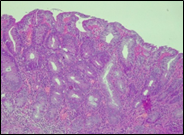

According to the degree of dysplasia, the premalignant lesions were described as follows: 106 (59.5%) with mild dysplasia, 48 (26.8%) with moderate dysplasia, and 24 (13.5%) with severe dysplasia. When grouped according to the WHO classification (2019), the premalignant lesions exhibited low-grade dysplasia in 154 (86.5%) patients and high-grade dysplasia in 24 (13.5%). Figure 6 shows different morphopathological forms of premalignant lesions from the series of patients included in the study.

A | B | C |

D | E | F |

Fig. 6 Morphological subtypes of conventional adenomas according to the WHO classification (2019) A, B – tubular adenoma with moderate epithelial dysplasia (A - HE stain, ×100; B - HE stain ×200); C – villous adenoma with moderate epithelial dysplasia (HE stain, x100); D – tubular adenoma with high epithelial dysplasia (HE stain, x200); E – tubulovillous adenoma with high epithelial dysplasia (HE stain, x200); F – tubulovillous adenoma with low epithelial dysplasia (HE stain, x200) | ||